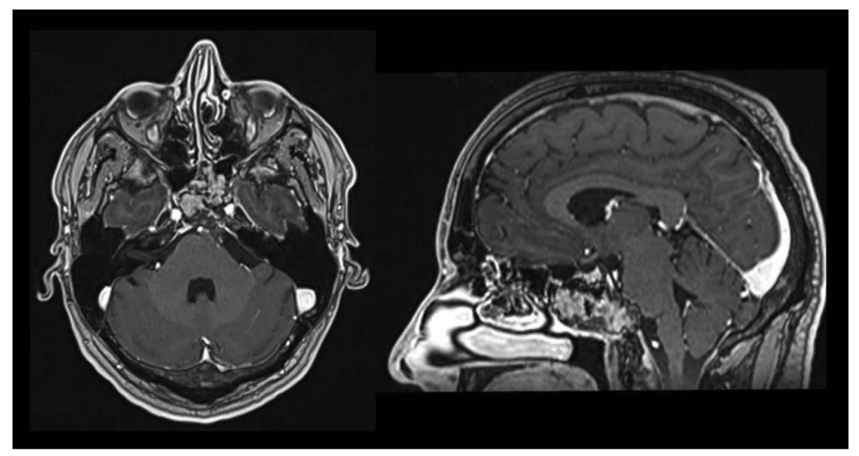

A、B:术后 CT 轴位及矢状位,绿色显示单鼻孔入路,鼻腔完整性得以保持;鼻中隔、上颌窦、后组筛窦及左侧蝶窦间隔均完整。

C:为抵达肿瘤外侧部分,已行左侧颈静脉结节(JT)磨除。

D:蝶窦被颅腔化并以自体脂肪填充,鼻黏膜缝合;肿瘤全切除,未见脑脊液漏。

分别在术后 1 周行 CT 及 MRI、2 个月行二次 MRI 复查,结果均提示肿瘤全切除。组织病理学示 WHO I 级。

术后 2 个月 MRI 轴位及矢状位示:脑膜瘤已完全切除,脑干复位良好。